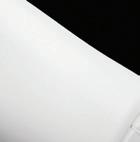

A 75-year-old female patient with diabetes and end-stage kidney disease (ESKD) presented with progressive right second toe swelling ulceration with gangrene and rest pain (Figure 1). There was extensive osteomyelitis and underlying tissue injury which required a planned amputation of the second toe. We were consulted prior to amputation for angiography, which demonstrated patent inflow vessels but severe BTK tibial disease. The baseline angiogram is shown in Figure 2. There was no inline flow to the foot, with occlusion of the anterior tibial, posterior tibial and peroneal arteries (Figure 2a). There was reconstitution of the peroneal artery, with partial filling of the posterior circulation via the posterior communicating artery. There was reconstitution of the anterior circulation with a visible small dorsalis pedis artery (Figure 2b).

Procedural overview

Given the angiosome of the tissue loss, we elected to pursue opening the anterior tibial CTO. Access with a 5F, 70cm sheath was used from a contralateral femoral approach. Using a 0.014” microcatheter and wire escalation, we were able to cross into the true distal lumen of the distal anterior tibial circulation using a 12-gram tipped guidewire (Figure 3a). A 2.5mm Shockwave E8 was used for multiple treatments along the entire length of the CTO segment (Figures 3b, 3c). Post IVL therapy, angiography showed brisk flow through the anterior tibial and into the distal anterior circulation of the foot (Figures 4a-c). This improvement in circulation allowed for this patient to undergo her planned second toe amputation with primary close (Figure 4d).